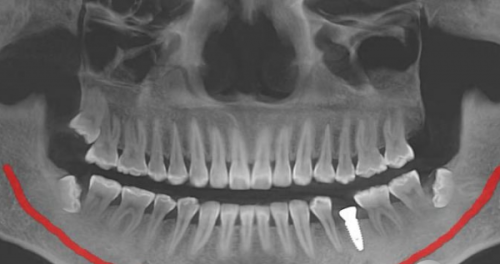

种植牙是合肥美奥口腔医院的特色项目之一。医院拥有精良的种植牙设备和技术,能够为患者提供高质量的种植牙服务。在种植牙过程中,医生会根据患者的口腔情况和身体状况,选择更适合的种植体,确保种植牙的成功几率和使用寿命。说到种植牙,就不得不提到合肥美奥口腔医院的陈国庆医生。陈医生是医院的从业多年种植骨干医生,他拥有多年的种植牙临床经验,擅长各种复杂的种植牙手术。他对待每一位患者都非常认真负责,会耐心地为患者解答疑问,制定更适合的治疗方案。在他的努力下,许多患者都成功地拥有了健康的牙齿。